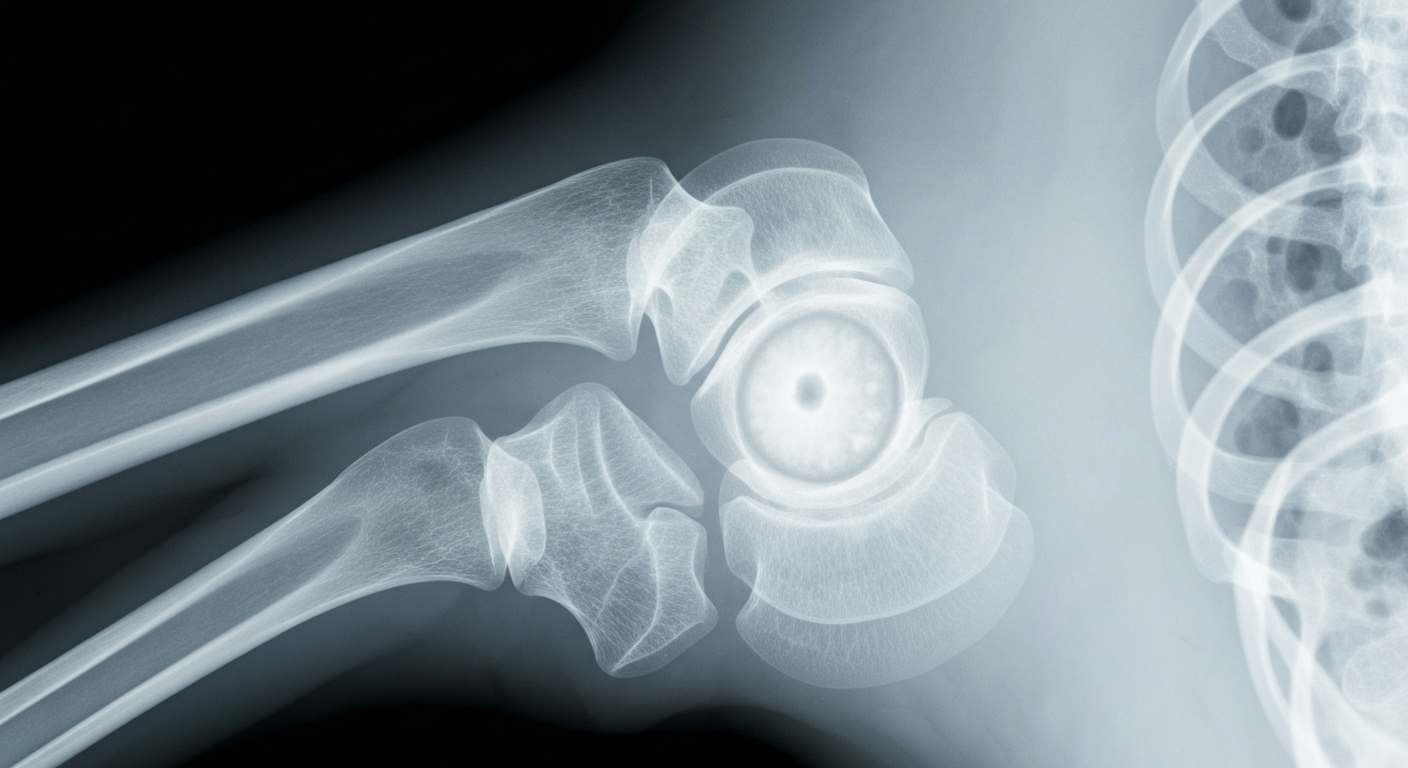

Ewing sarcoma and osteosarcoma are rare but aggressive cancers that primarily affect children, adolescents and young adults. While survival rates have improved for some pediatric cancers in recent decades, outcomes for patients with relapsed or metastatic sarcomas remain poor, making the development of new treatment options crucial.

The Phase II clinical trial, known as BCC023, will assess the safety and effectiveness of DFMO in combination with standard treatments, as well as DFMO used alone in certain patient groups, for Ewing sarcoma and osteosarcoma. DFMO works by blocking an enzyme called ornithine decarboxylase (ODC), which plays a key role in cell growth and division, potentially slowing or stopping the growth of cancer cells.